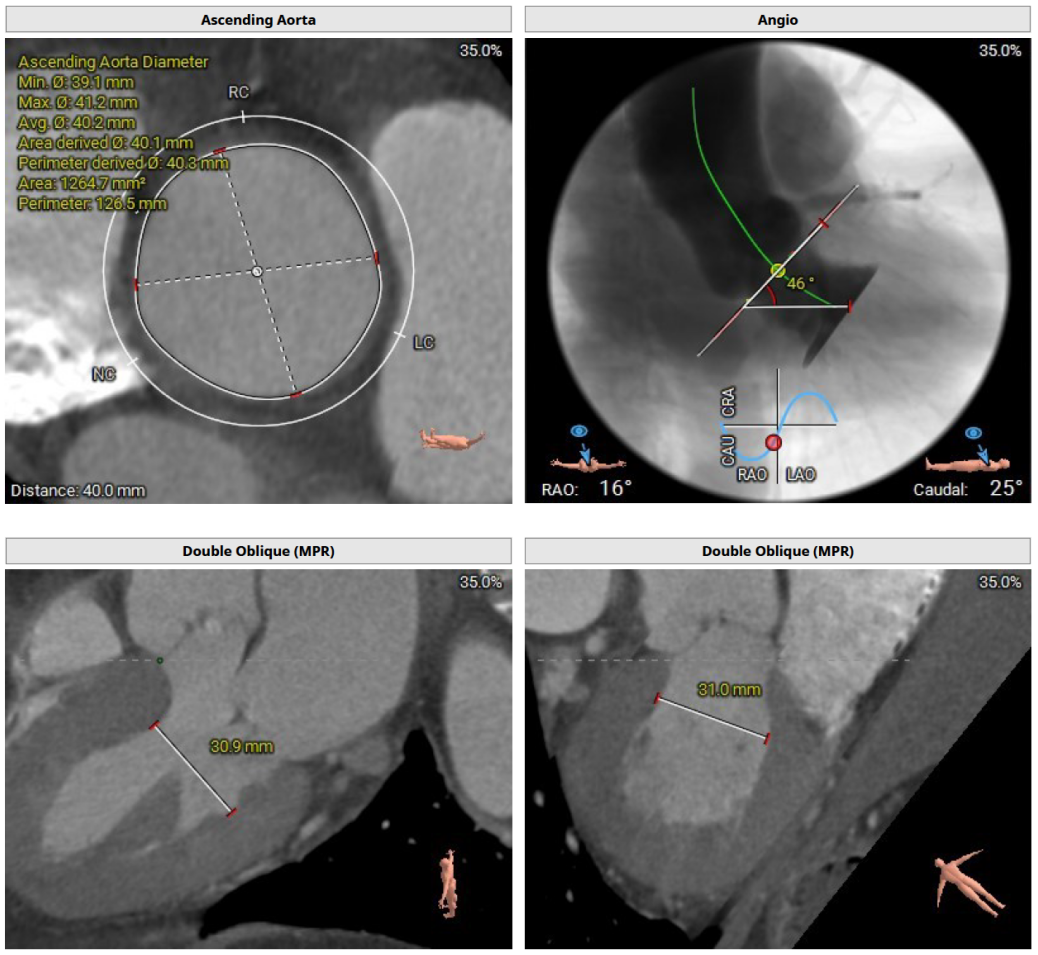

CT评估及手术策略

患者为三叶式主动脉瓣,重度反流。瓣叶交界轻度钙化。瓣环周长76.3 mm,平均径24.3 mm。LVOT周长77.3 mm,平均径24.0 mm。瓣上3.8 mm、5.0 mm、8.9 mm处空间为76.8 mm、82.8 mm、78.3 mm。STJ 周长105.7 mm,高度23 mm,升主周长126.5 mm 增宽、瓦氏窦大。综上所述建议TAV 27 瓣膜。左右冠高度15.6 mm、17.2 mm相对瓣膜支架可,冠脉风险低。股动脉入路血管轻度迂曲,双侧股动脉分叉高度可。腹主动脉、双侧髂总动脉散在钙化斑块。右侧股动脉平均内径最小6.3mm,左侧股动脉平均内径最小5.8mm,建议选择右侧股动脉为主入路。

本例患者是一个非常理想的纯反流病例。术前CT分析,瓣环-流出道都是24左右,直筒型,瓣上结构看,瓣环上2mm,4mm,8mm大概都是在25左右,而且有轻度钙化。也就是说,我们可以把从流出道-瓣上8mm这么长的一个距离作为锚定区,选择一个没有腰的瓣膜会很合适。窦管结合部33,升主动脉40左右,升主动脉能提供的锚定力就很少了。角度不大46°,通常纯反流都合并横位心,横位心因为瓣膜不同轴,会放大瓣环大小,而这个病例正好角度不大,也是一个有利因素。综合以上分析,我们团队决定使用微创的二代瓣膜,27号,0位释放。手术中起搏180降压,缓慢释放,瓣膜基本没有移位,在确认锚定后,逐步降低心率,释放瓣膜张力后脱钩,达到完美的手术效果。